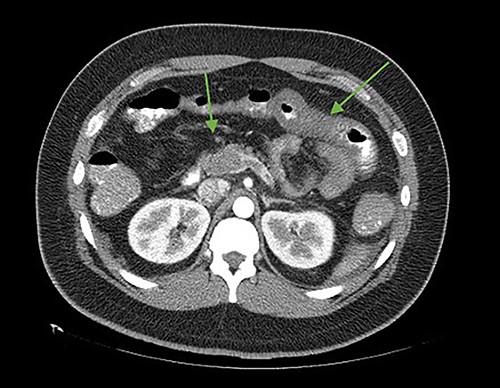

The patient was reoperated by laparoscopy, finding segmental thrombosis from 200 cm to 50 cm of the Treitz ligament, with edema and interloop free fluid without perforation (Figs 3 and 4). Lateral resection and entero–entero anastomosis were performed with manual stapler, subtracting 440 cm of intestine with adequate coloration. Later he was admitted to the Intensive Care Unit, treated with low molecular weight heparin at a full anticoagulation dose, maintaining an INR of 2 and a partial thromboplastin time of 80 s. He presented adequate evolution starting a liquid diet on the fourth postoperative day, new laboratories reported hemoglobin of 11 g/dl, 12 700 leukocytes/mm3, platelets 225 000/mcL, INR of 2. He was discharged on the fifth day with rivaroxaban treatment for 6 months.

Laparoscopic view of intestinal thrombosis and free fluid in the cavity.